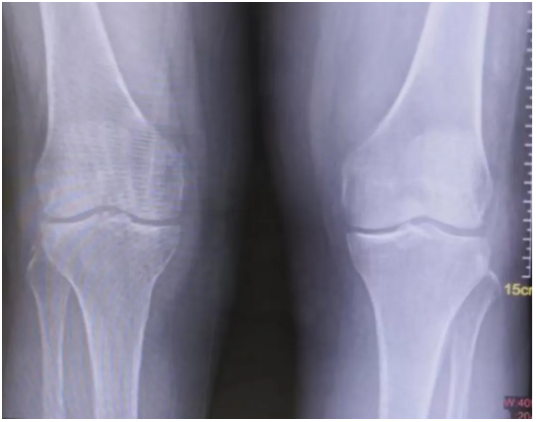

X光检查发现,黄阿姨的双膝关节间隙变窄,提示双膝关节炎,触诊发现双侧大腿外侧和小腿外后侧肌肉硬得像石头。